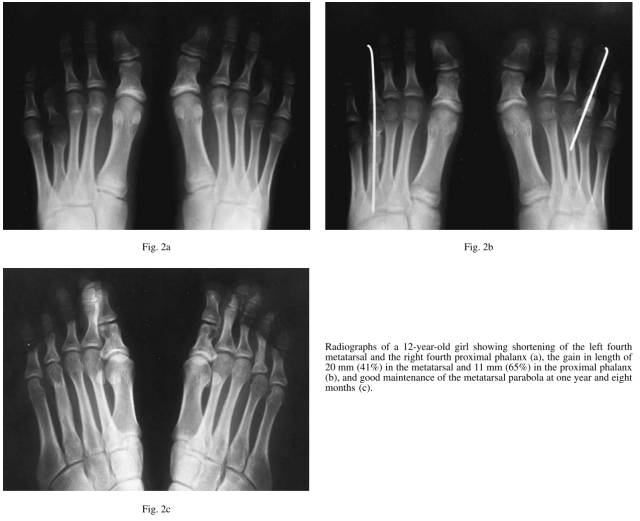

在1989年到1995年,我们在21例患者41例足趾,其中跖骨34例,近节趾骨7例。为了获得理想的长度,其中跖骨短小的患者有6例也进行了趾骨延长。所有的患者都是女性,平均年龄在16岁,10到36岁不等。所有的病人抱怨外观不好看,其中有10例伴有行走时相邻的跖骨头疼痛。有11例患者双边受到影响,其中第四跖骨短小10例,第一跖骨短小1例。在10例双边影响6例是第四跖骨,2例是第一和第四跖骨,一例是第一第三第四跖骨。在19例患者中,我们使用了髂骨植骨。在两例双边第一和第四短小,我们短缩了第二和第三跖骨,把骨块填塞到第四跖骨。3例患者有家族史,四例同时伴有手指短小,其中2例是双手,2例是同侧手。术后随访平均2.1年,从1到6.5年不等。

背侧纵行切口,锐性分离骨间肌。伸肌健分离开,暴露出短小的跖骨,从跖骨中段横断,1.14 or 1.57mm纵穿到末节趾骨,这是为了防止跖趾关节和趾间关节在延长的过程中的半脱位。我们逐步撑开20-30分钟逐步延长,降低软组织的张力。通常一次性延长可以轻易达到7-8毫米。逐步撑开延长一次大约延长接近1.5毫米,维持3分钟。自体髂骨取出后克氏针固定到远近端跖骨或者跗骨之间。

膝下行走石膏固定,石膏和克氏针在术后7-10周去除(拍片先确诊是否愈合),术后12周允许负重行走。近节趾骨延长和此类似。

我们的逐步延长技术通过逐步的持续放松的拉力延长20-30分钟,然后达到需要的长度21毫米,每次延长1.5毫米固定3分钟左右,不需要Z字延长肌腱和VY推进皮肤,没有发生血管神经的问题。

牵张成骨是通过外固定架的逐步延长,我们是通过术中逐步撑开获得满意的长度。我们通过对截骨处持续撑开20-30分钟包括周围的组织。在34例跖骨中通过我们的方法获得了平均14毫米延长,和牵张成骨的长度差不多,牵张成骨13-15毫米。牵张成骨会有关节半脱位,虽然可以通过纵行克氏针固定减少并发症。我们研究中没有发现跖趾关节半脱位。